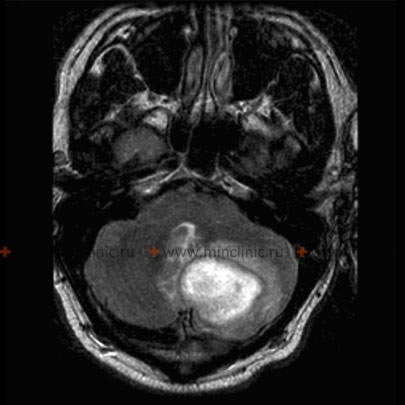

მაგნიტურ-რეზონანსული ტომოგრაფია ტარდება თავის ტვინის აბსცესის ეჭვზე.

- მრტ არის სასურველი გამოსახულების მეთოდი ტვინის აბსცესების დიაგნოსტიკისთვის.

CT და MRI ტომოგრაფია |

ნაკლებად გამიჯნული ანთება | CT: სქელი რგოლის ფორმის გამოკვეთა MRI: T1 ჰიპოინტენსიური, T2 ჰიპერინტენსიური |

გარსს შემოვლებული ნეოვასკულარული რეტიკულარული ქსელი | CT: თხელი რგოლის ფორმის გამოკვეთა MRI: T1 ჰიპოინტენსიური — შეშუპება/ცენტრი, ჰიპერინტენსიური — კაფსულა, T2 ჰიპერინტენსიური — შეშუპება, კაფსულა და ცენტრალურად შეზღუდული დიფუზია |